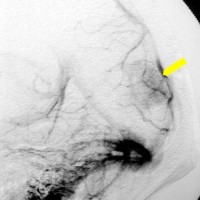

40代女性の後頭部傍矢状洞部の硬膜に発生したグレード3です。腫瘍周囲の強い浮腫のために,頭頂葉のゲルストマン症候で発症しました。術前診断は髄膜腫でしたが,腫瘍内部にのう胞(液体が溜まっている)があり,髄膜腫としては典型的な画像ではありません。右側の血管撮影にみられるように,上矢状洞が一部狭窄して腫瘍が浸潤している所見があり,腫瘍が濃染します。腫瘍の周囲の脳には出血がありました。大脳鎌と上矢状洞の壁を含めて全摘出しました。